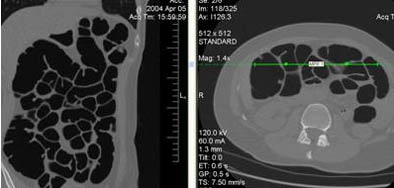

| A 44-year-old woman (first-degree relative of a colorectal cancer patient) underwent screening VC. Conventional colonoscopy two years earlier was incomplete due to dolichocolon. Immediately after prone decubitus positioning at the end of the exam, the patient reported abdominal pain, nausea, and stimulus to vomiting; a cold sweat was also observed. ECG did not show alterations of the cardiac cycle, blood pressure was normal, and a sustained bradycardia (50 bpm) was observed. VC data analysis confirmed the presence of dolichocolon and revealed overdistension of the small bowel in the supine (above) and in the prone decubitus positions (below). All symptoms resolved in 30 minutes. All images courtesy of Dr. Emanuele Neri. |